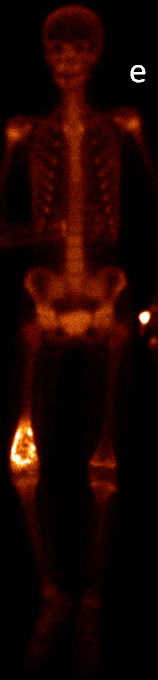

More complex anatomic structures (spine, the base of the skull, facial and hip bones) can be imaged more confidently with SPECT scans. On one hand, they provide a more accurate spatial localization and on the other, with their superior contrast resolution, they are able to differentiate lesions even if planar exams are negative or uncertain. SPECT-CT can characterize the CT morphology of the lesions with pathologic uptake. Thus, it is capable to provide a definitive diagnosis. (Figure 4.)

Image

a

b

c

d

e

4. Bone scintigraphy, prostate cancer. The image set shows the characterization of multiplex increased activity uptake. Posterior whole body scan (a). SPECT-CT coronal fusion images (b,d), CT examination (c,e). Sclerotic lesions in the pelvic bones are suggestive of osteoplastic metastases (b,c), small joint arthrosis at LIII-IV segments, more expressed on the left side (b,c), spondylosis on the right side at LIV-V segments (d,e). (The increased activity spot on the whole body scan, at the left cubital region, is correspondent to the paravasation of the iv. radiopharmaceutical.)